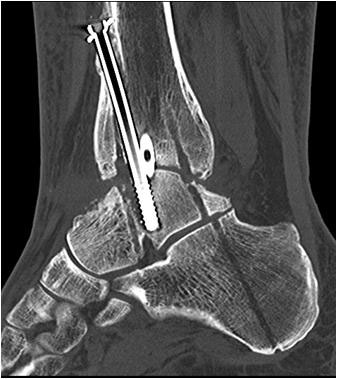

Von plantar aus nun Incision und Vorschießen eines 3er KDs durch Calcaneus, Talus bis in den Tibiaschaft hinein. BV-Kontrolle in beiden Ebenen. Bei korrekter Lage nun Eröffnungsbohrung. Wechsel auf einen Draht mit Olive. BV-Kontrolle in beiden Ebenen. Über den stumpfen Draht nun Aufbohren mit flexiblen Bohrern. Der letzte Bohrerdurchmesser sollte den Durchmesser des Arthrodesenagels um mindestens einen Millimeter übersteigen.

Implantation des Nagels und BV-Kontrolle (Video 5). Schließlich erfolgt die Verriegelung des Nagels über entsprechende Zielvorrichtungen. Bei einigen Nageltypen gibt es nageleigene Kompressionsmechanismen, die eine zusätzliche Drucksteigerung im Bereich der Arthrodeseflächen des ehemaligen oberen und unteren Sprunggelenkes erlauben (Video 6). Die abschließende BV-Kontrolle in beiden Ebenen sollte eine regelrechte Stellung der Arthrodese mit 90° - Stellung im Rückfuß, in der anderen Ebene mit einem Rückfußvalgus von ungefähr 5° zeigen.

• Primäre oder posttraumatische Arthrose des OSG und USG (Abbildung 1, Abbildung 2).

• Revision einer gescheiterten Fusion des OSG/ USG (Abbildung 3, Abbildung 4).